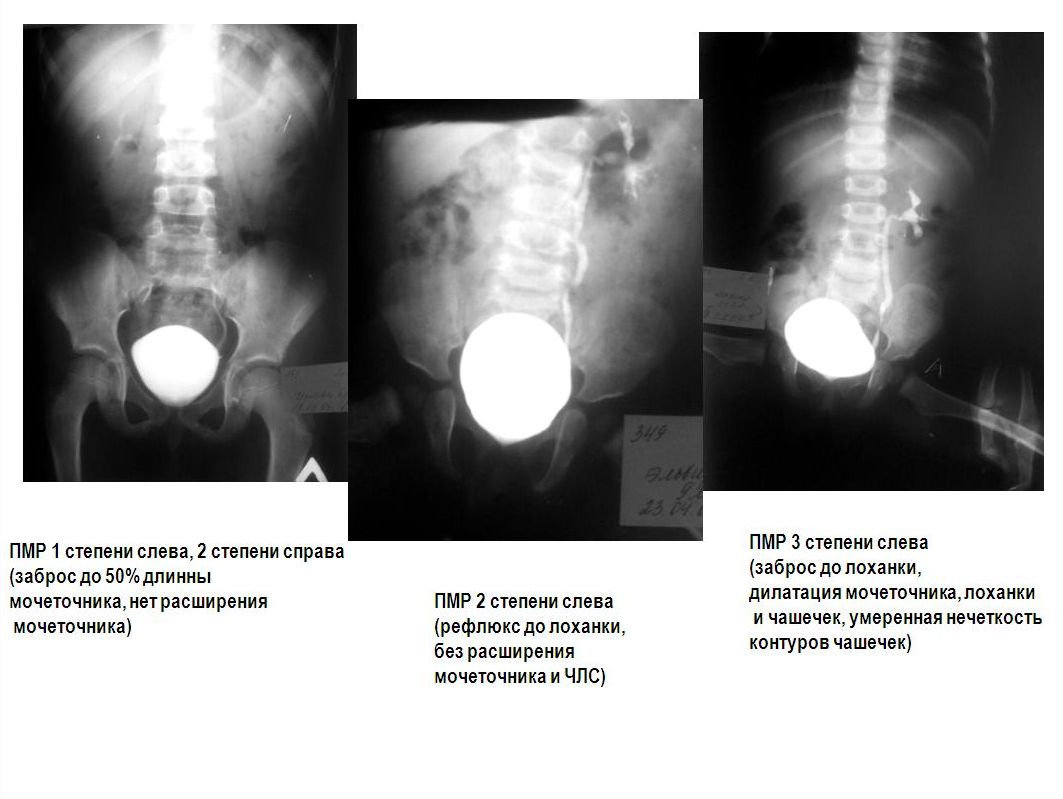

Рефлюксирующий мегауретер: Визуализация и медицинские изображения